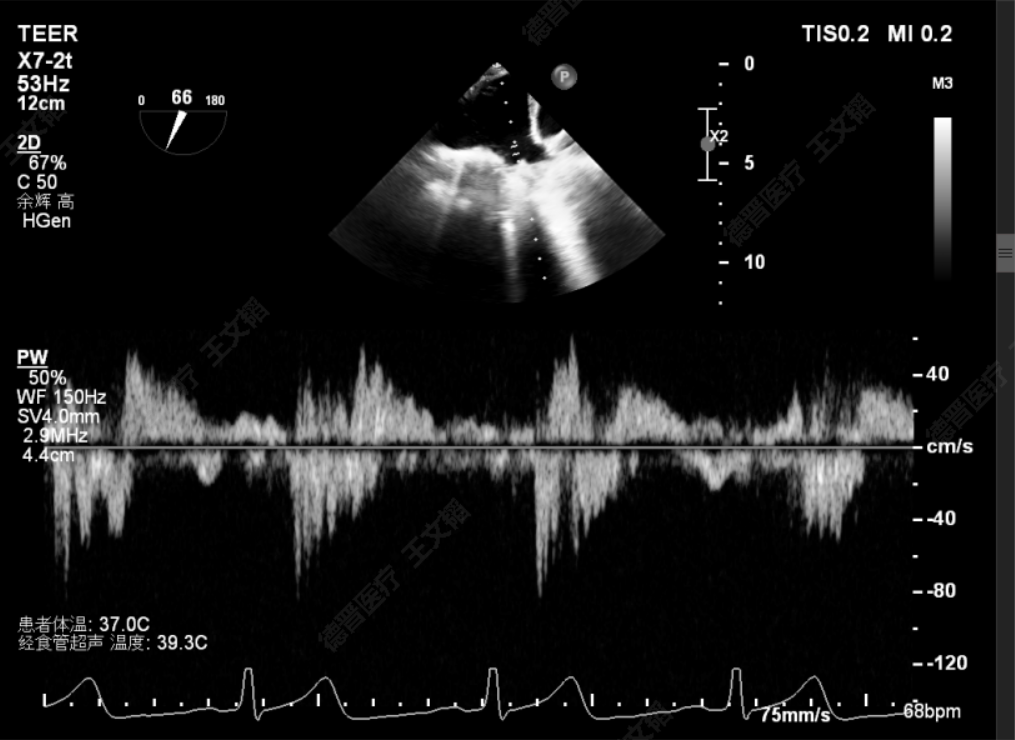

术前肺静脉逆流

术后肺静脉逆流

由于该患者情况特殊,潘宏伟教授、何晋教授团队通过讨论决定,先于脱垂正上方置入一枚长宽(XW0612)夹,再根据残余脱垂的情况决定是否置入第二枚夹子。术中团队利用DragonFly™刻度化旋钮及三段式可调节管身的设计,灵活调整二尖瓣夹系统,配合超声老师傅庆华教授的专业引导,成功将二尖瓣安全的打弯至二尖瓣瓣上。最后于2偏1区及2偏3区分别置入了两枚长宽(XW0612)夹。夹闭后反流由术前重度降低为Trace,跨瓣压差4mmHg,左房压由术前61mmHg降至术后27mmHg,肺静脉逆流几乎消失,效果立竿见影。

术前潘宏伟教授、何晋教授团队讨论决定,先于2偏1区置入一枚长宽(XW0612)夹解决最大的一处脱垂,再依次向内侧补夹子。术中房间隔穿刺高度:4.4cm,于2偏1区植入一枚长宽(XW0612)夹,夹闭后L侧无残余脱垂。再于M侧2区Side by side植入一枚长宽(XW0612)夹,夹闭后第一枚夹子较前稳定,M侧有残余脱垂。最后于M侧2偏3区植入一枚长窄(XN0412)夹,夹闭后残余功能性反流Trace,压差5mmHg,术毕,反流即刻由术前重度降低为Trace,左房压由术前45mmHg降至术后22mmHg,肺静脉逆流几乎消失,患者明显获益。